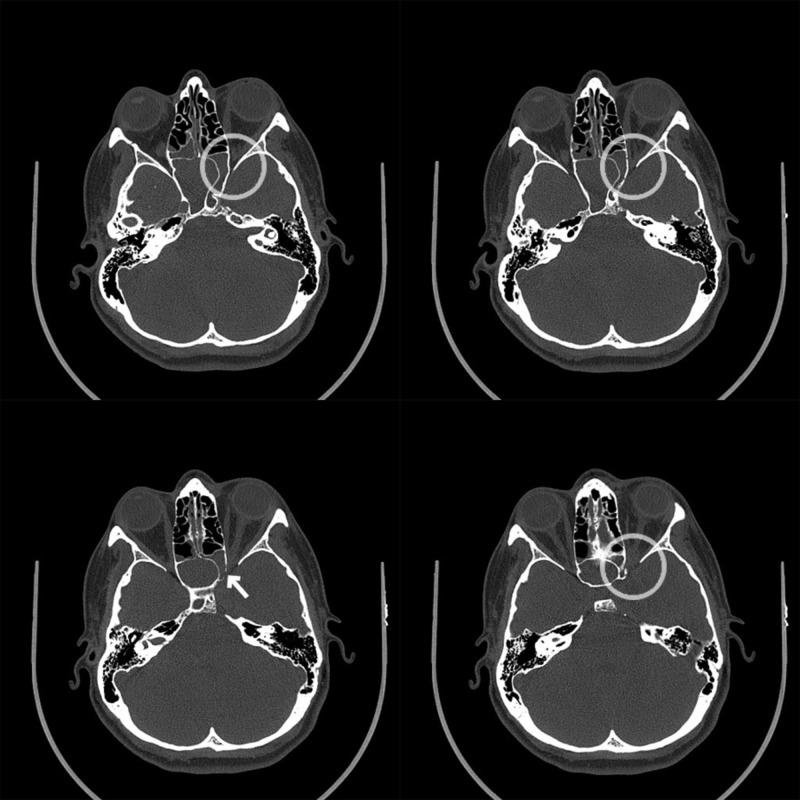

The emergency department is a challenging environment to practice medicine, primarily due to the pace and logistics of practicing emergency medicine. Cognitive errors and provider handoffs can lead to poor patient outcomes. By acknowledging and addressing cognitive errors, including premature closure, anchoring, and diagnosis momentum, we can potentially improve patient care. Additionally, by completing thorough, yet efficient sign-outs, as per The American College of Emergency Physicians' (ACEP) "Safer Sign Out Protocol," the chances of a poor outcome are further reduced. Below, a case of "migraine headache" is presented, highlighting cognitive errors and the risks associated with provider hand-offs in the emergency department.

急诊科是一个充满挑战的行医环境,主要是由于急诊医学的工作节奏和后勤保障。认知错误和医护人员交接班可能导致患者预后不良。通过认识并处理认知错误,包括过早下结论、锚定效应和诊断惯性,我们有可能改善患者护理。此外,按照美国急诊医师学会(ACEP)的“更安全的交接班协议”完成全面而高效的交班,可进一步降低不良后果的发生几率。以下展示了一个“偏头痛”病例,突出了急诊科的认知错误以及与医护人员交接班相关的风险。